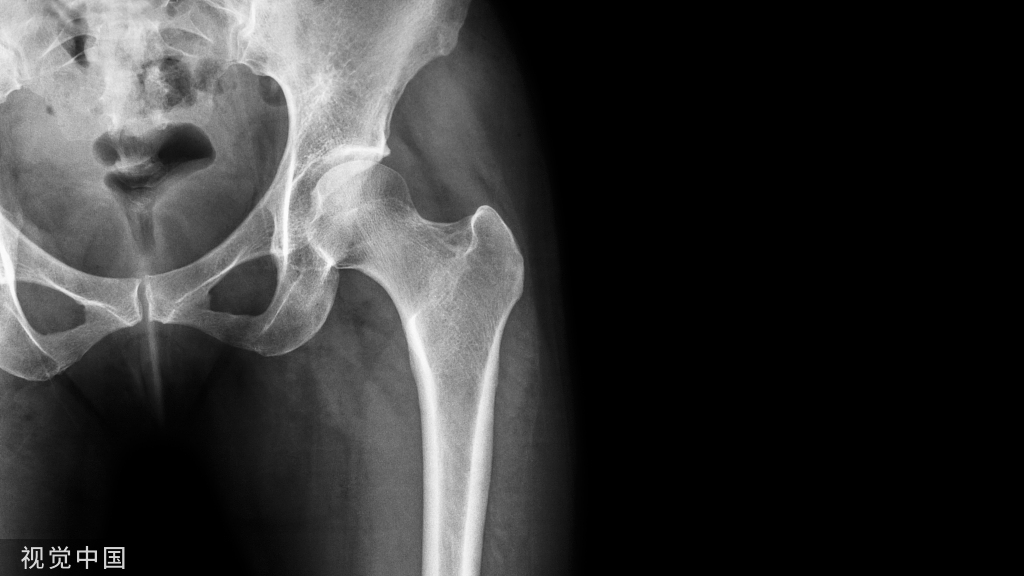

1、对骨科常见的并发症如骨筋膜室综合征的临床表现诊断标准及处理原则认识不足或处理时不果断造成严重后果2、在对创伤的诊疗过程中重视骨折轻视并发症及合并症,可能会造成严重的后果3、手术操作过于轻浮,随意性代替医疗规范的程序4、手术的定位错误导致二次手术5、诊断的定性错误导致过度治疗6、对患者伤情了解不全面造成漏诊,延误治疗最佳时间7、骨折内固定钢板螺钉或其它内固定材料断裂的处理不及时8、手术切口遗留异物

患者,男,20岁,因车祸致右小腿开放骨折1小时来院,门诊检查见伤口长13cm有活动性出血,骨折端外露,立即急症行清创血管神经探查,术中见胫前动脉及神经轻度挫伤,胫后血管神经未探及损伤,胫骨中段粉碎性骨折,远端向后成角,清创后用钢丝将胫骨骨折端捆扎,复位及逐层缝合,术后可触及胫后动脉搏动,足部皮肤感觉及足趾运动正常。术后第1-4天体温在38-39°C,给于抗生素及脱水药物治疗,第5天伤口感染并发胫前动脉及腓深神经坏死,(病历中此处无日期及记录人签名),伤后8天转入其它医院后病历记载膝关节以下感觉丧失,足趾活动丧失,足背动脉搏动消失,诊断1右胫骨开放性骨折术后感染2右小腿骨筋膜室综合征肌肉广泛坏死。

对患者伤情了解不全面造成漏诊,延误治疗最佳时间。此类事例较多患者,女。50岁。因车祸入院左大腿皮肤裂伤出血,局部骨干畸形,骨摩擦感,有异常活动,X线检查左股骨干骨折,左胫骨平台骨折,脑外伤。当日给予清创缝合,左股骨干骨折复位钢板固定,3周后又行左腕骨切除,左尺桡关节复位钢钉内固定,术后6周出院,出院后多次回该院复查,1年后再次入该院行左股骨内固定、左桡骨钢钉取出,术后拍片发现左股骨颈骨折,骨折向上移位4cm,半月后诊断左股骨颈陈旧性骨折在外院行人工全髋关节置换术。

高能量创伤易发生漏诊本案例属于高能量创伤致多发伤,由于临床检查不仔细,造成多处漏诊,其中股骨颈骨折的漏诊长达20个月,